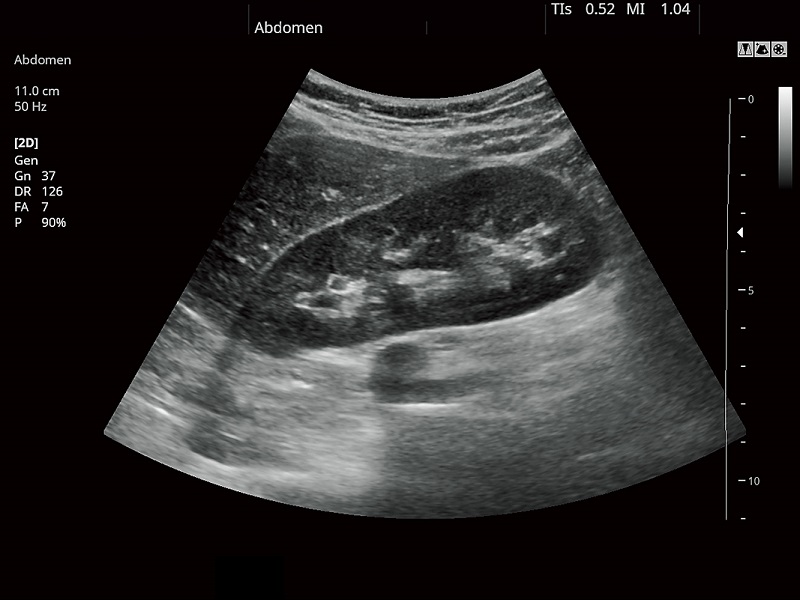

FUJIFILM FUTUS – Ultrasound System

FUTUS features great imaging technologies to support a clear view and confident diagnoses.